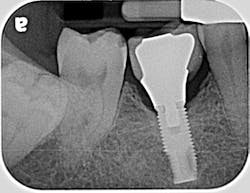

If the occlusal forces delivered to the implant-abutment-crown complex exceed the screw’s clamping ability, this may result in either its loosening (figures 1a and 1b) or, in more severe situations, fracturing of the screw (figures 2a–2c). Clinicians often indite the occlusion as being the primary culprit for the problem; however, in a number of instances, this may not be the case. The cause of screw loosening could also be due to using aftermarket parts, which do not have the precise fit of those made by the manufacturer of the implant.7